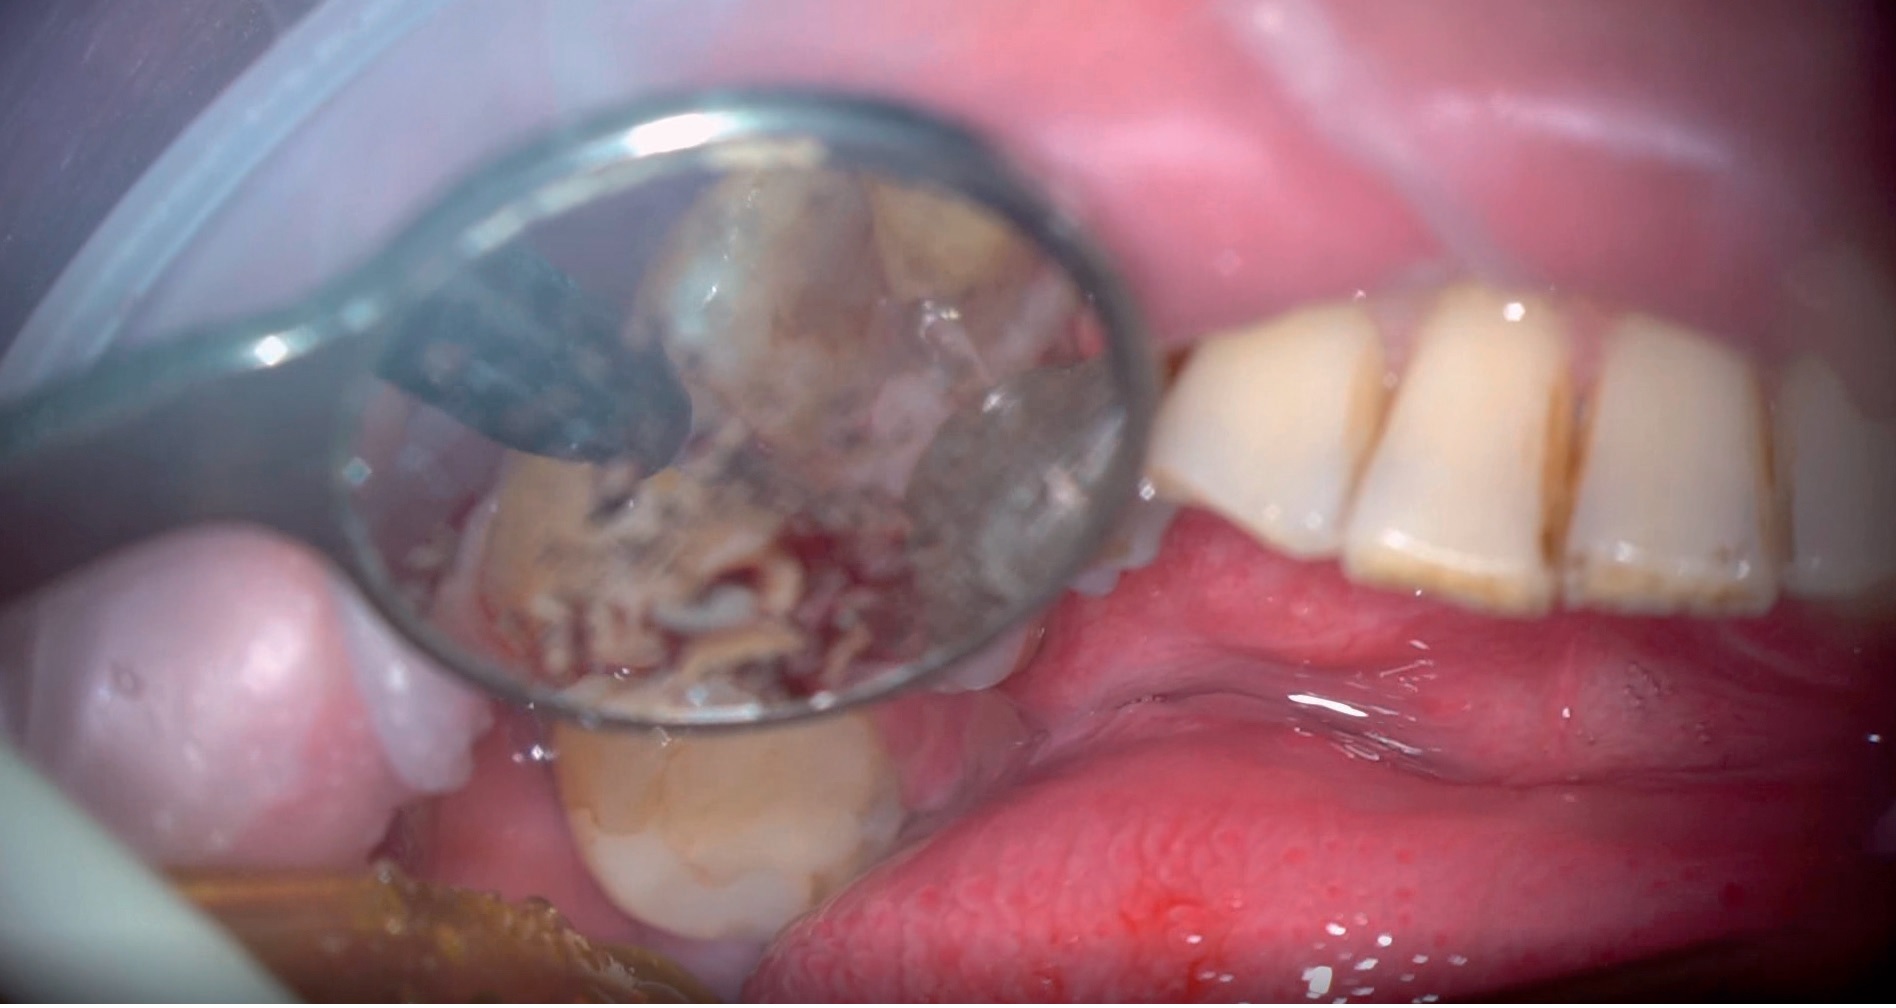

Artykuł przedstawia opis przypadku leczenia kanałowego zęba 21 z przewlekłym, zaostrzonym stanem zapalnym tkanek okołowierzchołkowych oraz inwazyjną resorpcją przyszyjkową zewnętrzną stopnia IV wg klasyfikacji Heithersaya, przekraczającą swoim zasięgiem 1/3 przykoronowej części korzenia zęba. Leczenie kanałowe przeprowadzono jednoseansowo wraz z równoczesną chirurgiczną ekspozycją zresorbowanej okolicy przez podniesienie płata od strony podniebienia oraz rekonstrukcją zniszczonych tkanek materiałem kompozytowym. Do usunięcia ziarniny zapalnej, opracowania ubytku oraz aktywacji roztworów płuczących zastosowano laser Er:YAG. Laser Nd:YAG zastosowano w celu dodatkowej dezynfekcji systemu kanałowego oraz stymulacji procesu gojenia (LLLT).

A case report of root canal treatment of tooth 21 with chronic exacerbated inflammation of the periapical tissues and invasive external cervical resorption grade IV according to the Heithersay classification, exceeding 1/3 of the parapenticular part of the tooth root. Root canal treatment was performed on a single session with simultaneous surgical exposure of the resorbed area by lifting the flap from the palate and reconstruction of damaged tissues with composite material. An Er:YAG laser was used to remove the inflammatory granulation tissue, prepare the cavity and activate the rinsing solutions. The Nd:YAG laser was used for additional disinfection of the root canal system and stimulation of the healing process (LLLT).

Film 1. Usuwanie ziarniny zapalnej.